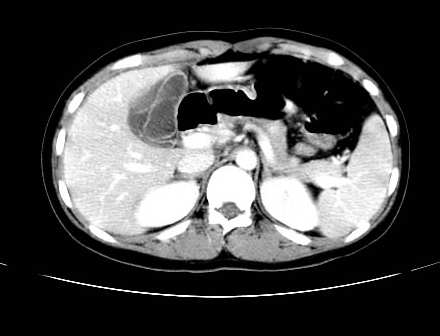

女 16岁  右上腹痛一天,无其他不适

肿块最大径位于十二指肠降段与水平段移行处,并且与肝脏压迹呈“0”形征,可以考虑位于肝外并与胃肠道关系紧密,考虑胃肠道间质瘤(gist)可能较大,须除外神经节起源肿瘤。

肿块与十二指肠关系密切,支持间质瘤诊断.肝脏与结肠均为受压改变.

右下腹巨大肿快,密度不均匀,内见坏死低密度区,边界清楚,与周边胀器明显有分界,未见强化,多考虑来源于间叶组织的良性肿物.

我坚决反对您的观点,该病例定位:横结肠肝曲与升结肠之间的肠系膜及部分肠壁。请看下图:

病灶巨大,少部分向肠腔内生长,大部分向长腔外生长。其密度不均匀,增强显示明显不均匀强化,并见有大片状始终不强化的不规则坏死液化区。虽然病灶中上部形态尚可,病人又如此年轻,但中下部形态、密度、强化特点强烈提示为恶性病灶。综上,我考虑本病例为:恶性胃肠道间质瘤。